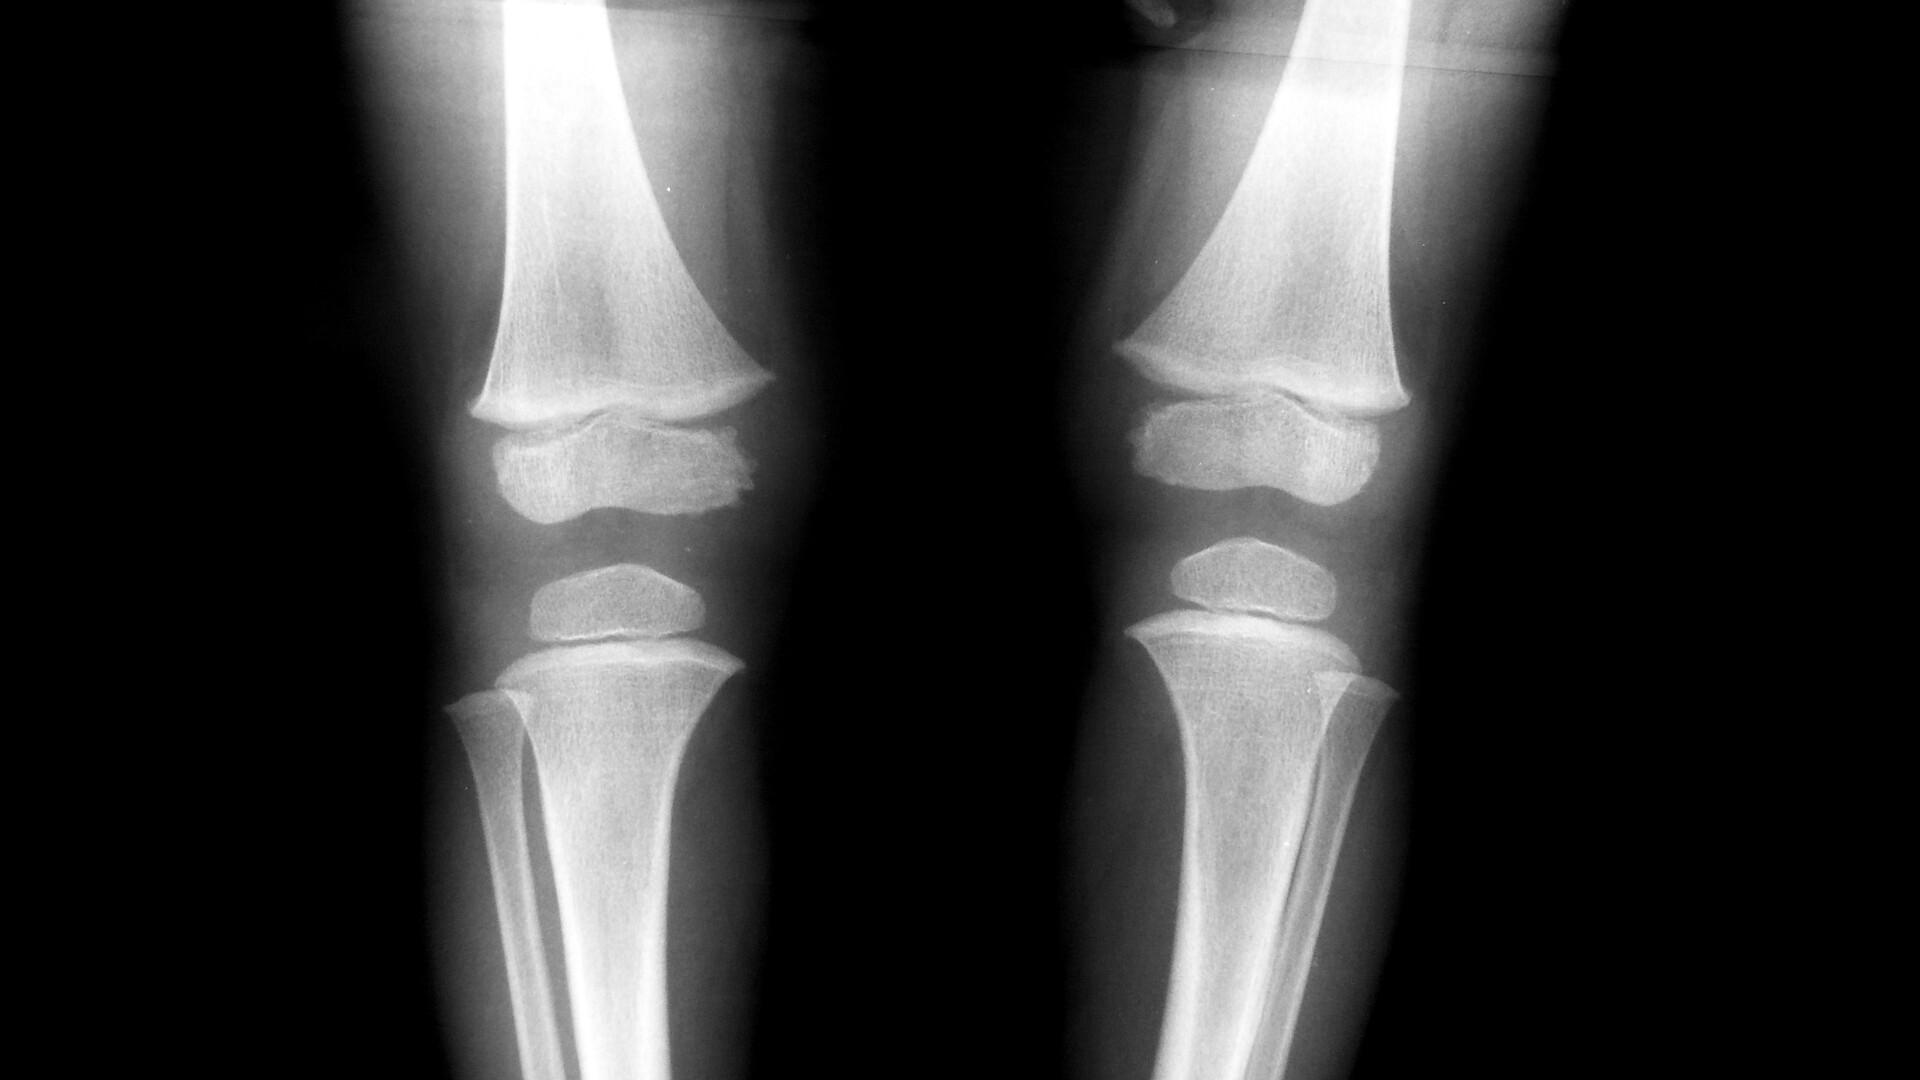

市面上的防曬乳液從臉部到身體,甚至是頭髮防曬的產品層出不窮。不過,內地一名28歲女子為追求皮膚白皙,不論天氣和季節,只要外出就必備太陽傘,防曬液每天要塗5、6次,再加上日常飲食不規律,導致維生素D嚴重缺乏,結果患上佝僂病(Rickets),最後連食物都無法咀嚼。

根據《新浪新聞》等內地媒體報道,杭州市第一人民醫院皮膚性病科醫生鄧琳表示,該名28歲女子如此嚴密的防曬措施,加上日常飲食不規律,令她嚴重缺乏維生素D,患上俗稱「佝僂病」的軟骨病,發展到後來連食物都無法咀嚼。鄧琳指出,過度防曬導致骨質疏鬆的病例不算普遍,很多患者除了長期不曬太陽,往往還存在一些飲食上的缺陷,種種因素疊加到一起,才會導致病情嚴重。